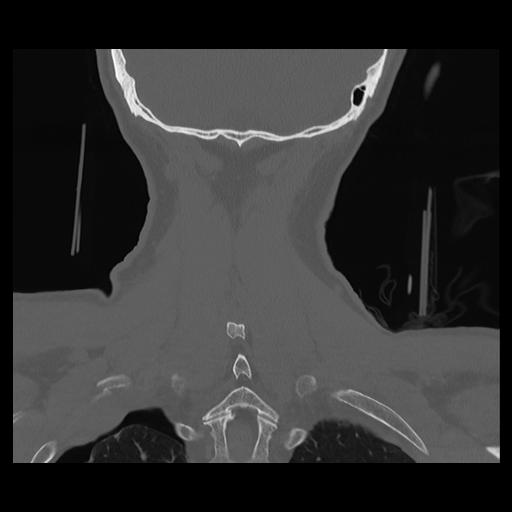

16 HUESO,,Coronal,2.000,HUESO,Coronal,